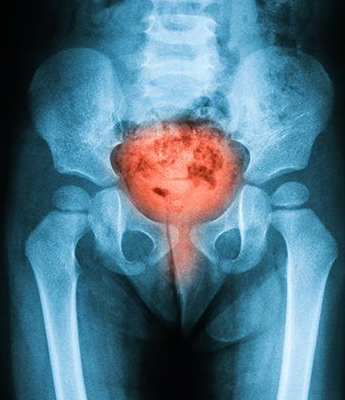

The prostate gland is a small, walnut-sized exocrine gland located at the base of the bladder. It plays a vital role in the male reproductive system by producing a significant portion of semen and providing nourishment to sperm, essential for their transport and protection during ejaculation. Disorders of the prostate, which are common in men over the age of 45, can significantly impact prostate function and overall health. Conditions such as Benign Prostatic Hyperplasia (BPH) cause the prostate to enlarge and may lead to urinary difficulties, while Prostatitis, an inflammation often resulting from infections or other causes, can produce symptoms like pelvic pain and urinary discomfort.

Prostate Cancer, a serious condition involving the development of cancerous cells in the prostate, is another critical concern. Regular consultations with a urologist are crucial for maintaining prostate health. Urologists provide valuable screenings, expert advice, and tailored treatment recommendations to address prostate disorders effectively. Early detection and management of these conditions are essential for preserving quality of life and ensuring optimal prostate function.